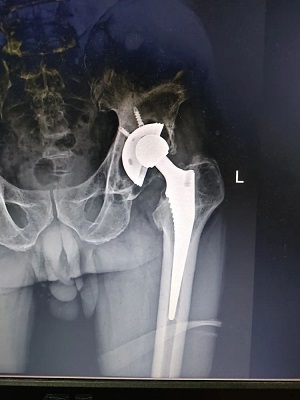

手术前

68岁的刘老伯,十年前因股骨头坏死,在我院行髋关节置换术治疗,术后恢复良好,没过多久就行走自如,与常人无异。

但今年以来,刘老伯置换关节位置突然出现疼痛症状,且疼痛渐进性加重,逐渐影响行动,于是老伯来到医院检查。首诊医生欧阳玉龙在了解病情后基本心里有数,建议老伯先拍个片子看看。

果不其然,CT片显示,患者置换关节半脱位松动,髋臼底部骨质明显吸收。显然,患者关节置换十余年,到了人工关节使用寿命年限,需要再次翻修置换。